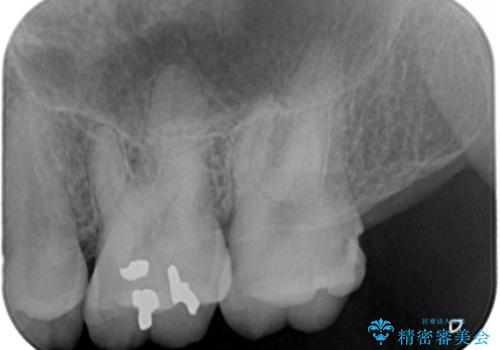

- 奥歯に物が詰まりやすいということが主訴で来院され、歯全体が虫歯になっていたので被せ物にて治療を行なった。

仮歯を装着した時点でものが挟まる症状は改善されました。

虫歯は綺麗に取り切れています。